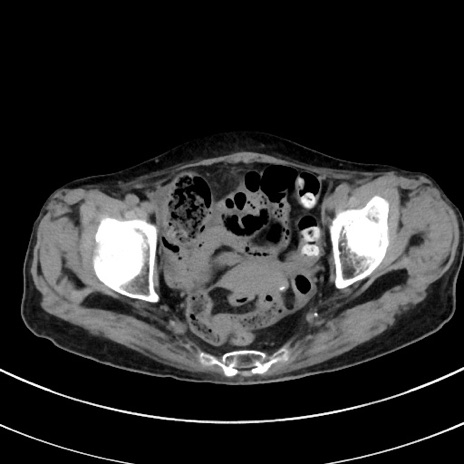

症例33(横断像)

【症例】70歳代 女性

【主訴】心窩部痛

【現病歴】延髄病変の精査・加療にて神経内科入院中。本日より心窩部痛あり。

【身体所見】右下腹部を中心に圧痛と反跳痛あり。

【データ】WBC 10900、CRP 0.02